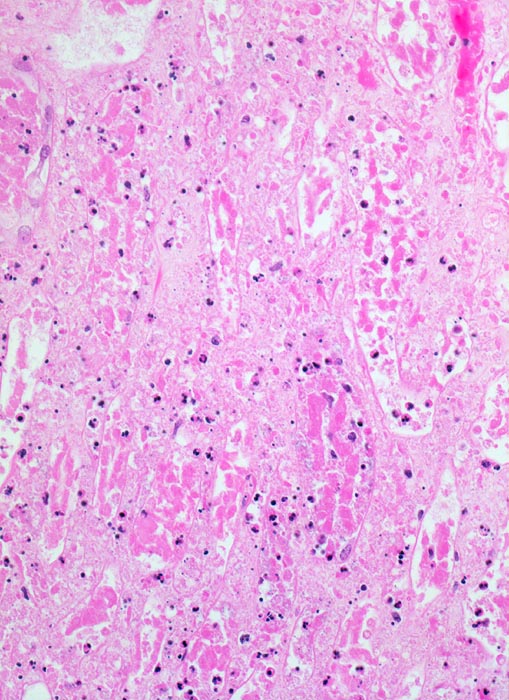

Akute Infarkte bilden histologisch scharf begrenzte kokardenförmig aufgebaute Herde mit zentraler Koagulationsnekrose umgeben von einem Saum neutrophiler Granulozyten. In der Peripherie ist das partiell geschädigte Gewebe ödematös hämorrhagisch und enthält dilatierte hyperämische Gefässe. Die Nekrose wird durch neutrophile Granulozyten und Makrophagen abgebaut und durch Granulationsgewebe ersetzt, welches zu einer gefässarmen Narbe schrumpft. Die äusserste Rindenzone bleibt infolge der Kollateralversorgung durch Kapselgefässe oft vom Infarkt ausgespart. Infarktnarben können wie alle Narben verkalken.